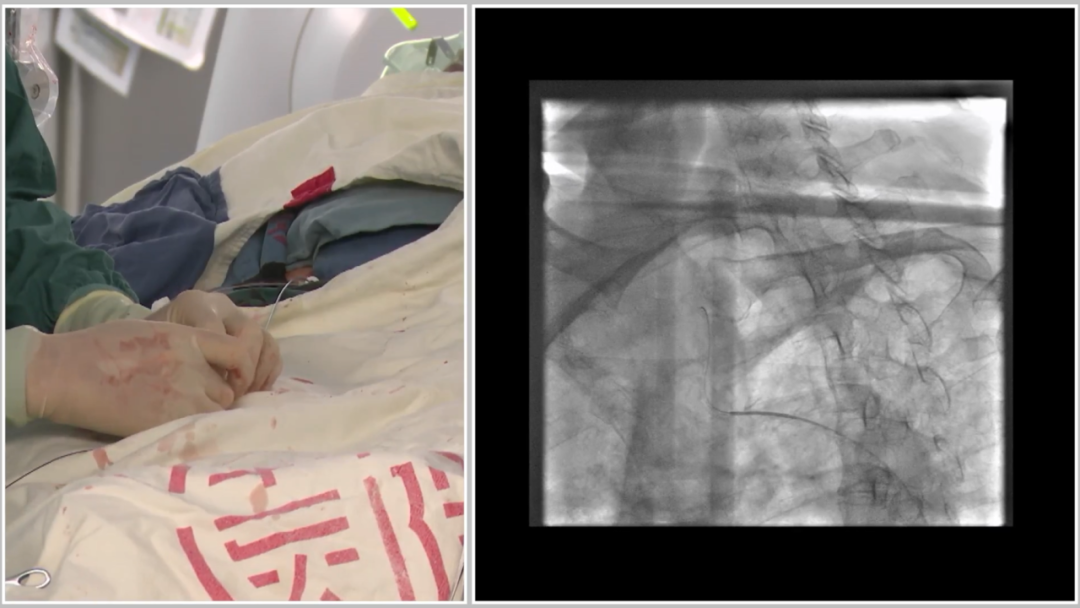

★ 术前准备与通路建立

穿刺右侧股动脉,置入6F90cm长鞘,全身肝素化抗凝;

主动脉弓造影确认分型为Ⅰ型弓,为后续操作提供解剖参考